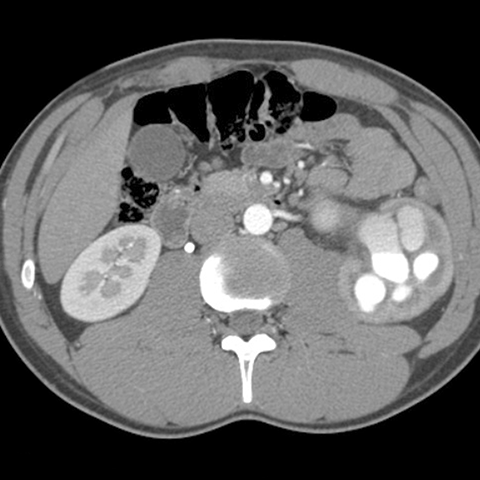

Congenital obstruction of the ureteropelvic junction (UPJ), axial CT [3 of 4]